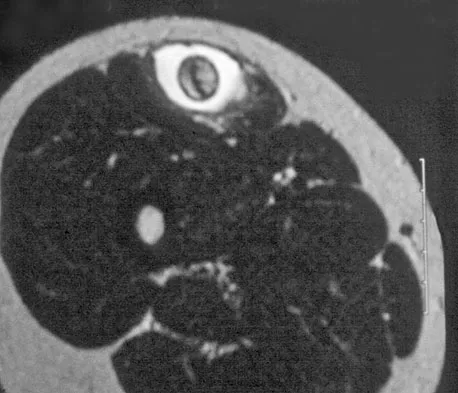

Question 24High Yield

A 28-year-old man reports knee stiffness, swelling, and a constant ache that is worse with activity. Examination reveals an effusion, global tenderness, and warmth to the touch. Flexion is limited to 110 degrees. Figures 48a through 48d show sagittal T1-weighted, sagittal T2-weighted, axial T1-weighted fat-saturated gadolinium, and axial gradient echo MRI scans. Based on these findings, what is the most likely diagnosis?